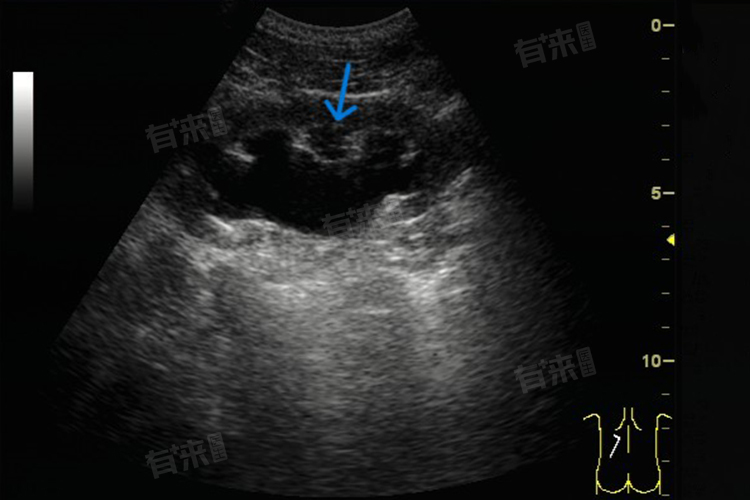

在超声、CT 等影像学检查中,如果膀胱壁增厚呈现不规则形态、局部突出、血供丰富等异常特征,癌症的可能性也会增大。如果发现膀胱壁增厚,应及时就医,进行全面的检查和评估,以便早期发现和治疗潜在的疾病。